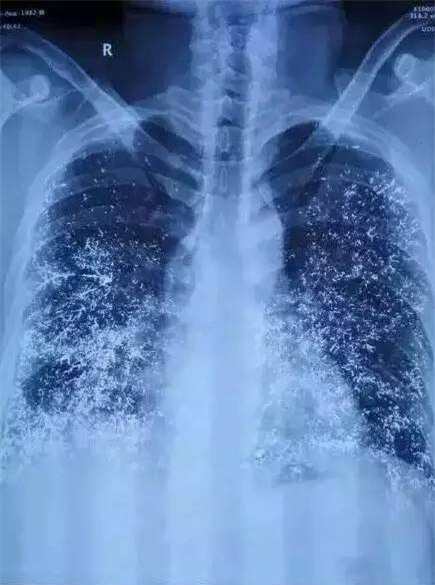

Nhiều cơ quan nội tạng của nạn nhân bị tổn thương nghiêm trọng.

Hành vi của Lưu Linh đã khiến bạn trai cô bị trúng độc nghiêm trọng, tổn thương tim, phổi, thận, đại tràng và tủy ở cấp độ 2, đến nay khả năng loại thải thủy ngân vẫn còn chậm. Với tình trạng này, nạn nhân Trần Hạo cần điều trị ít nhất 4 năm, thời gian trị bệnh có thể kéo dài 20 năm hoặc cả đời.